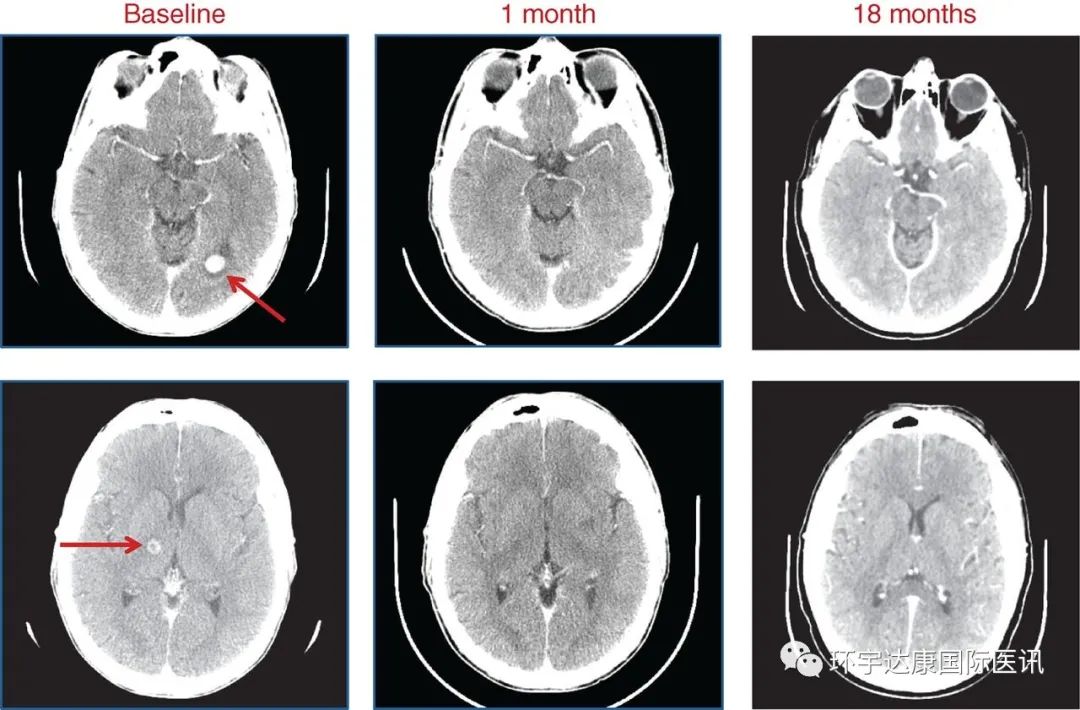

比如这位幸运的患者,确诊为SQSTM1–NTRK1重排肺癌,同时出现了严重的脑转移,有15~20个病灶,下面的CT 显示了左侧枕叶(顶部)和右侧丘脑(底部)的转移(红色箭头)。患者接受了恩曲替尼的治疗,在使用 entrectinib 1 个月和 18 个月时做了CT复查,显示在治疗18个月时,患者的病灶已经全部消失,(数据截止时)评效获得 CR(完全缓解)。